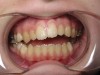

Mouth breathing has also been associated with dental malocclusions in children.2 Zicari and colleagues' analysis of 71, 6- to 12-year-old mouth breathing children revealed a 72.5% incidence of reduced transverse diameter of the maxilla and increased vertical dimension, a 32.5% incidence of cross bite, a 43.7% incidence of skeletal class II malocclusions, and a 90% incidence of atypical swallowing patterns. The results showed a strong correlation between oral breathing and malocclusions, which manifests as both dentoskeletal and functional alterations, leading to a dysfunctional malocclusive pattern (Figure 1 through Figure 3). The study concludes that “this dysfunctional malocclusive pattern makes it clear that the association between oral breathing and dental malocclusions represents a self-perpetuating vicious circle in which it is difficult to establish if the primary alteration is respiratory or maxillofacial. Regardless, the problem needs to be addressed and solved through the close interaction of the pediatrician, otorhinolaryngologist, allergologist, and orthodontist.”

(1.) In children, mouth breathing with low tongue posture can result in narrow maxillary arches, dental crowding, tongue scalloping, and anterior open bites. Images courtesy of Kevin Boyd, DDS, MSc.

Figure 1

(2.) In children, mouth breathing with low tongue posture can result in narrow maxillary arches, dental crowding, tongue scalloping, and anterior open bites. Images courtesy of Kevin Boyd, DDS, MSc.

Figure 2

(3.) In children, mouth breathing with low tongue posture can result in narrow maxillary arches, dental crowding, tongue scalloping, and anterior open bites. Images courtesy of Kevin Boyd, DDS, MSc.

Figure 3